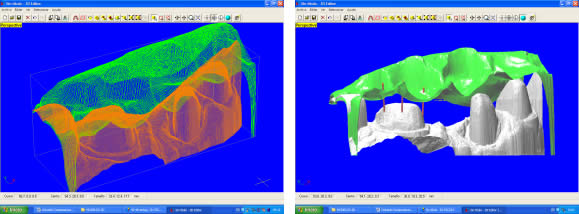

Introducción.- En oclusión, existen varios campos de aplicación básica para la digitalización. Hablamos, preferentemente, de la digitali- zación tridimensional. Recordemos que esta palabra es sinónimo de medición y –como tal- auxilio en esta rama odontológica tan necesitada de precisión. La digitalización tridimensional consistirá en el registro de la posición espacial, de un finito número de puntos, determinando sus coordenadas -x,y,z-. A menor distancia entre cada punto se conseguirá como resultado un objeto virtual con mayor detalle, coincidente con el real. Con cada triada se podrá formar una superficie, que continuada con la generada por el resto de la malla de puntos, completarán la forma del objeto. Este es el origen de donde partimos para establecer el concepto básico de las revolucionarias aplicaciones 3D. Se parte así del denominado escaneado tridimensional: Escaneado Superficial de un objeto real -> “Nube de Puntos” -> “Malla de Alambre” -> Superficie del Objeto Virtual. Con los modelos dentarios, impresiones o registros de oclusión, virtuales (en la pantalla del ordenador), realizaremos ahora, mediante un programa informático, la manipulación simulada, mediante computadora, para la realización del estudio y diseño de la oclusión. La Oclusión Computarizada (OC) –dentro de la más amplia Odontología Computarizada- comprende, hoy, fundamentalmente, tres fines: 1º)- El Estudio, Diagnóstico y Plan de Tratamiento Asistidos por Ordenador. 2º)- El Encerado Computarizado. (Por RP –Rapid Prototyping-, Prototipado Rápido, o por CAM –Computer Assisted or Aided Machining or Manufacturing-, Maquinado Asistido o Ayudado por Computador). 3º)- La Restauración y Confección de Prótesis Computarizada. (Por CAD-CAM, -Computer Assisted Design – Computer Assisted Manufacturing-, Diseño y Fabricación Asistidas por Computador). La Odontología Computarizada tiene entre sus numerosas secciones, ésta de oclusión, considerada primordial en el trabajo clínico habitual, desde la que nos relacionamos con la ortodoncia, cirugía implantológica, tecnología protésica y prostodoncia. Cada uno de los citados fines de la OC necesita partir de un escaneado tridimensional de los objetos a tratar: elementos del sistema dentario (arcadas) –de forma directa, en la misma boca del paciente-, o modelos dentales obtenidos por una impresión material de éstas y su posterior escaneado –o forma indirecta, fuera de la boca del paciente-. El escaneado se puede realizar con variados dispositivos, resultando procedimientos de distintos tipos y con diferentes características, clasificados simplificadamente como: A) Escaneado de contacto, háptico: B) Escaneado sin contacto: Tomando una imagen del objeto, marcado por líneas o cuadrículas luminosas proyectadas sobre su superficie, que se deforman con ella, analizándose luego digitalmente. El escaner se considera aquí un analizador trigonométrico del objeto, que registra su imagen, marcada mediante un rayado por luz –normalmente láser- (que permite, mediante software, obtener las coordenadas espaciales de multitud de puntos, que son agrupados en unidades de tres, constituyendo los vértices de una superficie triangular, que sumándose a las vecinas, llegarán a representar la envuelta completa del objeto y así su forma volumétrica o tridimensional). C) Combinado. Externo e Interno. Los escáneres suelen resultar, actualmente, poco económicos, y aunque van decreciendo en coste, están –para estas fechas- en un nivel que suele partir como mínimo de los 8.000 euros; siempre dependiendo del procedimiento de registro empleado, tamaño y precisión del escaneado. Existen: A) aparatos integrados en sistemas dentales, desarrollados específicamente para nuestro campo, de comprobada eficacia y de alto coste económico; B) dispositivos de uso general, aplicables a los propósitos de la odontología, de complicada adaptación pero de muy bajo coste relativo; C) múltiples posibilidades para la construcción de un escaner propio, casero y económico, que pueda, con suficiente experiencia, llegar a funcionar para uso profesional, gracias a la existencia de suficiente información de la tecnología empleada, ampliamente divulgada y de fácil desarrollo; útiles para fines diagnósticos. En oclusión necesitamos el 3D, pero también el 4D. Sumamos aquí a las tres coordenadas espaciales de cada punto del objeto, otra más, la cuarta dimensión: el tiempo. Dado que un objeto móvil, lo es por la temporalidad de sus posiciones en el espacio. Así se registrarán y analizarán digitalmente los movimientos mandibulares para conseguir la articulación y reproducción de la función masticatoria. Para esto se han aplicado determinados registros, mediante sensores de posición o por receptores de actividad muscular, como los electromiógrafos, o el más específico articulador virtual, del que se encuentran diferentes productos de software, englobados –como complemento necesario- en los programas que acompañan a los distintos sistemas de cad-cam dental. Desde el escaneado, o transformación u obtención del objeto real en cuerpo 3D, numérico, adquirido para ser estudiado y manipulado de forma digital, virtual, en el computador, continuamos con otras vías, ahora posibles, de enorme potencial, desde el estudio y planificación a la fabricación protésica. Así van a ser expuestas a continuación: A) La planificación; B) el encerado; y C) la fabricación. A) -Estudio, Diagnóstico y Plan de Tratamiento Asistidos por Ordenador. La planificación de la rehabilitación oclusal, puede iniciarse: A-1) Por Registro Estático Morfológico Computarizado, del aparato estomatognático y sistema dentario. Que puede realizarse: I) A partir de Escaneado Extraoral. I-a) Escaneado Volumétrico (CT–tomografía computarizada-) (O mejor, CBCT –tomografía computarizada de haz cónico-, de menor radiación y coste, con aparatos diseñados específicamente para uso dento-máxilo-facial ). I-b) Escaneado Superficial –de los modelos de estudio- y Registros Oclusales-. II) A partir de Escaneado Intraoral. II-a) Escaneado Volumétrico (CT local, o CBCT local, que se están desarrollando para aplicación retroalveolar). II-b) Escaneado Superficial –de las caras oclusales del sistema dentario-. A-2) Por Registro (Estático Morfológico Computarizado) de Huellas de Oclusión (o Registros Oclusales), para análisis de contactos intermaxilares, estáticos -y menos o indirectamente los movimientos mandibulares-. Mediante escaneado superficial de registros, sus modelos 3D, y combinación o no, con el Papel de Articular Electrónico (T-Scan). A-3) Por Registro Dinámico Funcional (fisiológico) Computarizado: I) Registro Computarizado (Integrado) de los Movimientos Mandibulares –electropantográfico o cinematográfico-. Por sensores o marcadores de posición. II) Registro Computarizado (Integrado) de la Función Muscular –electromiográfico-. A-4) Por Integración Informática de varios de los Registros citados. B) -Encerado Computarizado. Es el modelado o diseño virtual en la pantalla del ordenador y su realización en material de patronaje (como la cera u otro de similar; económico, modificable, transformable y rápido), que puede realizarse por: B-1) Por RP –prototipado aditivo- o B-2) por CAM –maquinado sustractivo-. Como pensamos en el concepto clásico, la realización de un encerado diagnóstico es clave para una rehabilitación oclusal correcta. Además el encerado servirá para la confección de: a) una posible férula radiológica y quirúrgica, b) una referencia para el tallado, la prótesis o rehabilitación temporal y el patrón para la definitiva. Se llevará a cabo, en dos etapas: 1ª) Etapa de creación del patrón. Elaboración virtual en la pantalla del ordenador. Necesitando el software apropiado, CAD. 2ª) Etapa de confección. Elaboración Real, mediante RP o CAM. 1ª) La etapa de creación virtual del patrón en la pantalla del ordenador, mediante un programa informático de diseño y manejo de objetos tridimensionales, (siempre partiendo de un registro previo, como el escaneado de los modelos), puede facilitarse con varias herramientas para: -Elaboración Virtual por Adición. 2ª) La etapa de confección, o elaboración real, mediante RP o CAM. -Confección por RP (Rapid Prototyping) –Prototipado Rápido-, de adición o construcción capa a capa, añadiendo una sustancia que se endurece, aumentando su nivel en superficie. La elaboración real por adición, es posible en un variado –pero limitado- tipo de materiales. -Confección por CAM (Computer Aided Machining) –Maquinado o Tallado Asistido por Ordenador-, de eliminación de sustancia o esculpido en un bloque sólido. La elaboración real por sustracción, es posible en un numeroso -y casi ilimitado- tipo de materiales. Existen gran cantidad de dispositivos que consiguen la fabricación y consecución física de un encerado real, a partir de su elaboración virtual, desde un escaneado y su diseño computarizado. Todos los sistemas denominados de cad-cam dental, en general, aunque no estén espe- cialmente dispuestos para ello, pueden dedicarse a este propósito; simplemente colocando un material de patronaje, como la cera, en lugar del material con el que se constituirá la prótesis definitiva. Pero, existen –también- sistemas espe- cialmente configurados para el trabajo en material de diseño, normalmente: ceras, resinas o compuestos, es lo que se denomina prototipado rápido (rapid prototyping). En la industria general, la fabricación de cualquier objeto en serie, requiere de estos procedimientos en las primeras etapas de elaboración para su producción. La más económica y reducida Impresora 3D o Sistema de Prototipado Rápido, que puede confeccionarnos unos maxilares, a partir de la tomografía, o un encerado diagnóstico, según el software disponible. Su precio actual 45.000 Euros. C) -Restauración y Confección de Prótesis Computarizada. (Por CAD-CAM). Es el modelado o diseño virtual en la pantalla del ordenador y su realización en material definitivo (como porcelana, titanio, aleación preciosa, u otro similar); poco económico, difícilmente o no modificable, ni transformable y que requiere de un tiempo adecuado, mucho mayor que el requerido para la confección del patrón de material plástico. Esto puede realizarse por numerosos dispositivos. Existen gran variedad de sistemas para el diseño y confección de restauraciones y prótesis. Son los denominados gene- ralmente SISTEMAS DE CAD-CAM DEN- TAL (Dental Cad-Cam System): (Entre estos sistemas encontramos los que también pueden planificar el tratamiento restaurativo y realizar el encerado diagnóstico con diseño y confección de un patrón oclusal; como hemos referido antes). Históricamente estos sistemas comenzaron con la década de los setenta -en 1971, con el Holodontography-Altschuler System-, y con el Sopha System de Duret, progresando enormemente hasta comienzos de los noventa. Durante esos veinte años, se potenció su desarrollo con el siguiente hito histórico que los encumbró, en su segunda década, por la aparición de los principales impulsores del cad-cam clínico comercializable -Mörmann y Brandestini, en 1981-, denominado Sistema Cerec. También se establecieron los principios de estos dispositivos con el DCS Dental System, el CAP System, el Minnesota-Rekow System, el Nissan Cad/Cam System, Automill y Microdenta System. El culmen del progreso se alcanzó a mediados de los noventa, con sistemas ampliamente comercializados y evolucionados hasta hoy: Procera, DCS Dental, o Cicero. En los siguientes diez años, se continuó perfeccionando los sistemas citados; hubo algunos sistemas no comerciales o de escasa difusión, o distribuidos moderadamente; repre- sentando un período hasta el 2000, con una pequeña depresión, en los años medios, por el declive en la extensión de estos productos, en relación al extraordinario futuro que se les auguraba, motivada por el alto coste de los equipos y las limitaciones en su potencia digital, en el que –aún y así- aparecieron sistemas como: Belledent, Cadim, Dentscan, CCD System, Cynovad, Digident-Girrbach, Decim y Etkon. La segunda revolución para la odontología por cad-cam se produjo con el comienzo del siglo. Ampliándose enormemente la cantidad de sistemas y alentándose una explosión del trabajo digital en odontología, con: Cercon-Degussa, Lava-3M-Espe, Cad-Esthetics System-Ivoclar, DDS, GC-Dental, Everest-Kavo y Bego. En estos momentos el futuro de la odontología se encuentra inexorablemente unido a estos aparatos. Para el clínico o el laboratorio dental es hoy imprescindible contar con ellos. Siguen nuevas apariciones, como el sistema Hint-Els, o el Evolution-4D, similar al Cerec, que fue el pionero, pero que todavía, a la fecha, se mantiene como el más versátil, modulable y práctico, con progresos como el facilitado trabajo de diseño tridimensional o el nuevo escaneado extraoral independiente. Los sistemas de cad-cam, están integrados por: un escaner que digitaliza el objeto dental, un ordenador con el software adecuado para el diseño virtual, y una máquina de tallado para la fabricación del objeto diseñado en un material determinado. Una relación actualizada, de gran número de los sistemas existentes se encuentra en “Aktuelle CAD/CAM Systeme”, en http://www.tu-dresden.de/medprothetik/computerzahn/CAD-CAM-Systeme.htm Factores clave en la Oclusión Computarizada-. La digitalización del estudio, diagnóstico y tratamiento de la oclusión, como la construcción o restauración de un sistema dentario óptimo para la correcta función masticatoria del aparato estomatognático, pretende facilitar y generalizar la excelencia en el trabajo clínico. Es una aplicación de preferencia informática porque pueden manejarse gran cantidad de datos, mediciones, relaciones geométricas, unidas a la tridimensionalidad y la movilidad de sus elementos, de una forma racional, lógica y científicamente fundamentada, aún partiendo de concepciones filosóficas o criterios sujetos a distintas escuelas de oclusodoncia. La digitalización de la oclusión pude llevar- nos a despejar supuestos sin evidencia científica, de la que adolece sectorialmente nuestro arte. Tenemos suficientes fórmulas, reglas y relaciones numéricas, aportadas por numerosos autores, que tienen que se recopiladas y que pueden así ser aplicadas. Yá que la digitalización recoge todos los datos métricos y posicionales (coordenadas de cada punto, con su x,y,z), del sistema dentario, se pueden establecer fórmulas matemáticas para que -siendo la z la determinante de la altura de un punto en el espacio-: una z máxima, de una pieza mandibular, esté más o menos próxima a una z mínima de una pieza maxilar; que un punto (de cúspide) -con una determinada x,y- maxilar, coincida con otro –con la misma x,y- mandibular, pero con distintas aunque casi idénticas z, dándose el contacto oclusal. Y de esta forma, con sucesivas relaciones (matemáticas) se construiría una oclusión tendente a la excelencia; matemáticamente desarrollada. Así podría confeccionarse, automáticamente, una oclusión geométrica, dando, por ejemplo, solamente: la posición base de cada pieza, la x,y de las cúspides de una hemiarcada, y la altura de su plano oclusal, y automáticamente se generarían las cúspides agonistas y antagonistas, y la morfología dental completa de ambas arcadas. Se tendrían que añadir los datos correspondientes a los dientes anteriores, a las ATMs y las fórmulas de relación de las pendientes. Distintos autores han desarrollado relaciones métricas en oclusión. Algunos han simplificado el proceso, como partida, para ir añadiendo variantes; así, pueden usarse valores standard, normales, del ángulo cuspídeo para fabricar la morfología oclusal en CAD/CAM, -cuando la creación del esquema oclusal es de novo-, según Hobo y Takayama; y el uso de varios valores fijos de partida, universalmente aceptados, en lugar de la medida directa de la pendiente condilar es, según los mismos autores, muy importante en el desarrollo extenso de los sistemas de CAD/CAM. Así, el procedimiento de «twin-stage» propuesto por estos autores, en su libro “Oral Rehabilitation”, proporciona una solución en la producción de una oclusión dinámica tridimensional para el CAD/CAM. Otra técnica, consiste en el encerado virtual, mediante un modelado CAM, siguiendo las etapas de Shillimburg, o Kuwata, elaborando paso a paso la morfología oclusal, orientada a su enfrentamiento con el antagonista, encaminando los volúmenes cuspídeos como en el encerado progresivo clásico, gota a gota. Se realizaría su construcción virtual en la pantalla del ordenador, pudiendo estar facilitada su manipulación, mediante “espátulas de encerado virtual”, utilizando los digitalizadores de brazo articulado, con los que se pueden disponer los volúmenes necesarios, en la posición espacial que se desee. No obstante, el modelado dental se puede realizar siempre, aunque sea a través del clásico ratón del ordenador, de forma virtual, con la imagen tridimensional en la pantalla, utilizando diferentes procedimientos, con el software adecuado: A) Automático, a partir de las reglas dentométricas, odontométricas y cefalométricas, relacionadas con la gnatología, tomando previamente los valores claves necesarios del paciente. B) Mediante diseño de la anatomía con trazado de los perfiles, líneas y curvas, que van a definir las superficies dentales. Trabajando bidimensionalmente, en base a cortes de la estructura a construir, que manipulada variando sus dos dimensiones, va a corresponderse con la morfología dental tridimensional, al establecerse un área de influencia y cambio en los cortes vecinos, y así alterándose el volumen dental completo. Este era el procedimiento de variación anatómica utilizado, durante dos décadas con el Sistema Cerec (el Cerec 1, Cerec 2 y Cerec 3), hasta la llegada del Cerec 3D. C) Mediante copiado de la cara oclusal ideal, realizada previamente en cera u otro material real, del diente, su registro oclusal o su antagonista, en el concepto original del Sistema CEREC, de construcción oclusal mediante Correlación –copiando un encerado previo- o Función –correspondiendo automáticamente a la cara oclusal del antagonista-. D) Mediante selección de dientes, individuales o en grupo (incisivos, caninos, premolares, molares, arcadas, hemiarcadas, sistema dentario, maxilares o mandibulares), de entre un grupo de archivos de modelos dentales tridimensionales virtuales, como una librería de objetos 3D. Como en la selección de las tablillas de dientes para la confección de las prótesis completas. Escogiendo tamaño y forma. Colocando cada pieza o bloque en su lugar, con la disposición espacial y oclusal correspondiente. E) Mediante la misma selección, antes citada, seguida luego de una transformación, como estiramiento o estrechamiento, u otras variaciones morfológicas, con las herramientas de edición del programa informático, hasta conseguir la oclusión que se pretende. F) Mediante encerado virtual, de adición progresiva de volúmenes anatómicos, en el concepto clásico de encerado gota a gota, con la metódica de P. K. Thomas, para restauraciones parciales, o de Kuwata, para rehabilitaciones extensas. El método de encerado es el que nos permitirá la construcción de una oclusión individualizada. Pero la necesidad de utilización de un articulador es evidente. Es presumible que se desarrollen nuevos instrumentos para la perfección de la oclusión computarizada, semejantes a los articuladores mecánicos tradicionales. Serán los denominados articuladores virtuales, (VA –Virtual Articulator-), o simuladores digitales de la articulación oclusal, consistentes en un programa informático, capaz de relacionar los modelos virtuales, permitiendo movimientos similares a los naturales del paciente: es la aplicación de la tecnología de la realidad virtual a la oclusión (VR –Virtual Reality-). Esto es lo que nos permitirá pasar de la fórmula empleada generalmente para el modelado oclusal, que suele ser estática y referida a un registro de las superficies antagonistas, a un sistema experto que reproduzca la relación completa de ambas arcadas, las articulaciones, y su combinación con los movimientos masticatorios: realizando la dinámica mandibular. Hoy en la mayoría de los sistemas de cad-cam, los trabajos oclusales se realizan, extensamente, basados sólo en el enfrentamiento con el antagonista, sin tener en cuenta la movilidad mandibular, las guias condilares o anteriores. Es como si realizásemos un encerado oclusal sin tener en cuenta los determinantes anteriores y posteriores, y trabajásemos en un articulador, no ajustable, o simplemente en un Oclusor o Verticulator, sin giro de cierre ni desplazamientos horizontales.El articulador virtual, por software, para el diseño oclusal en la pantalla del ordenador, aún no es empleado de forma generalizada en estos sistemas, pero ya se encuentran como aplicaciones en algunos de ellos. Uno de los pioneros se utiliza en el sistema Cynovad. Aquí, directamente relacionado con la confección de un encerado oclusal. Otros dispositivos electrónicos y digitales, de registro por ordenador, que podrían combinarse con la construcción plástica de la oclusión, en cera u otro material, solo se están utilizando para diagnóstico, o como complementos a articuladores mecánicos sofisticados; así podemos encontrar programas como Rosy32 Robot System (Diagnostic Articulator), de registro dinámico, el VirtSet, de diagnóstico y predicción oclusal-ortodóntica, o el ArtiKulator-Software (ver ArtiDemo), de programación virtual de un articulador, con elección del equivalente mecánico real (Sam, Artex, Kavo,…). Entre éstos, el sistema más completo desarrollado, con escaneado de modelos y registros, y correspondencia con la dinámica mandibular, obtenida por un arco facial cinemático, con sensores de posición y movimiento, es el DentCAM.Para clasificar los instrumentos de oclusión, consideramos muy completa la clasificación de los articuladores mecánicos, desarrollada en The International Workshop Occlusion, de 1972, University of Michigan: 1) Clase I – Sujetadores simples de modelos. Subdivisión A (Con movimientos verticales; Corelator, Verticulator). Subdiv. B (Con articulación de bisagra sin desplazamientos horizontales; Centric Relator). Conclusiones (parciales para esta primera parte).- El articulador virtual podría establecerse a partir del escaneado de un articulador mecánico seleccionado, a partir de un modelo construido íntegramente por CAD de forma virtual, o –idealmente- a partir de un patrón anatómico, individual, a partir de la radiología tridimensional (como la Tomografía Computarizada). A estas estructuras se les sumarán los datos necesarios para la función: relación intermaxilar –estática- (oclusal) y relación cráneo-mandibular dinámica (pendiente condílea y Bennett), con ayuda también del registro de la actividad muscular (electromiografía). A la clasificación de los articuladores antes expuesta, le podemos añadir ahora el Tipo V, constituido por los Articuladores Virtuales, o instrumentos informáticos que pueden reproducir la oclusión dental en el ámbito de la realidad virtual, que se desarrollan como programas informáticos concretos, de muy variada composición en sus elementos de software, y distintos por los diferentes tipos de registros que necesitan para su efectiva y precisa actuación. Dentro de este V grupo, a su vez, podríamos –paralelamente a la clasificación de los articuladores mecánicos-, establecer tantas subclases como las de los tipos y subclases de aquellos. Así habría de clase I, como ocurre mayoritariamente en los sistemas de Cad-Cam dental actuales, cuando utilizamos modelos dentales 3D y registros estáticos de antagonistas. Es éste el cambio que se experimentará en los próximos años, en la Oclusión Computarizada: la utilización generalizada de Articuladores Virtuales de clase III y IV. Bibliografía Cooper BC. Parameters of an optimal physiological state of the masticatory system: the results of a survey of practitioners using computerized measurement devices. Cranio. 2004 Jul;22(3):220-33. Reiss B. Occlusal surface design with Cerec 3D. Int J Comput Dent. 2003 Oct;6(4):333-42 Petrie CS, Woolsey GD, Williams K. Comparison of recordings obtained with computerized axiography and mechanical pantography at 2 time intervals. J Prosthodont. 2003 Jun;12(2):102-10. Kojima T, Sohmura T, Nagao M, Wakabayashi K, Nakamura T, Takahashi J. A preliminary report on a computer-assisted dental cast analysis system used for the prosthodontic treatment. J Oral Rehabil. 2003 May;30(5):526-31 Bernhardt O, Kuppers N, Rosin M, Meyer G. Comparative tests of arbitrary and kinematic transverse horizontal axis recordings of mandibular movements. J Prosthet Dent. 2003 Feb;89(2):175-9 Tsai HH. A computerized analysis of dental arch morphology in early permanent dentition. ASDC J Dent Child. 2002 Sep-Dec;69(3):259-65, 234 Ferrario VF, Sforza C, Serrao G, Schmitz JH. Three-dimensional assessment of the reliability of a postural face-bow transfer. J Prosthet Dent. 2002 Feb;87(2):210-5. Kerstein RB. Current applications of computerized occlusal analysis in dental medicine. Gen Dent. 2001 Sep-Oct;49(5):521-30 Kerstein RB, Wilkerson DW. Locating the centric relation prematurity with a computerized occlusal analysis system. Compend Contin Educ Dent. 2001 Jun;22(6):525-8, 530, 532 passim; quiz 536. Sohmura T, Kojima T, Wakabayashi K, Takahashi J. Use of an ultrahigh-speed laser scanner for constructing three-dimensional shapes of dentition and occlusion. J Prosthet Dent. 2000 Sep;84(3):345-52. Kerstein RB. Computerized occlusal management of a fixed/detachable implant prosthesis. Pract Periodontics Aesthet Dent. 1999 Nov-Dec;11(9):1093-102 Tarantola GJ. A computerized model for teaching various methods of positioning the condyles to centric relation. Gen Dent. 1999 May-Jun;47(3):308-12 Gsellmann B, Schmid-Schwap M, Piehslinger E, Slavicek R. Lengths of condylar pathways measured with computerized axiography (CADIAX) and occlusal index in patients and volunteers. J Oral Rehabil. 1998 Feb;25(2):146-52 Tamaki K, Celar AG, Beyrer S, Aoki H. Reproduction of excursive tooth contact in an articulator with computerized axiography data. J Prosthet Dent. 1997 Oct;78(4):373-8 Garcia Cartagena A, Gonzalez Sequeros O, Garrido Garcia VC. Analysis of two methods for occlusal contact registration with the T-Scan system. J Oral Rehabil. 1997 Jun;24(6):426-32 Matsui Y, Ohno K, Michi K, Suzuki Y, Yamagata K. A computerized method for evaluating balance of occlusal load. J Oral Rehabil. 1996 Aug;23(8):530-5 Giddon DB, Sconzo R, Kinchen JA, Evans CA. Quantitative comparison of computerized discrete and animated profile preferences. Angle Orthod. 1996;66(6):441-8 Matsui Y, Neukam FW, Wichmann M, Ohno K. A computerized method for evaluating distribution of occlusal load on implant-supported fixed cantilever prostheses. Int J Oral Maxillofac Implants. 1996 Jan-Feb;11(1):67-72 Hayashi T, Saitoh A, Ishioka K, Miyakawa M. A computerized system for analyzing occlusal relations during mandibular movements. Int J Prosthodont. 1994 Mar-Apr;7(2):108-14 Maness WL. Computerized occlusal analysis. J Can Dent Assoc. 1993 Aug;59(8):701-2 Edwards CL, Richards MW, Billy EJ, Neilans LC. Using computerized cephalometrics to analyze the vertical dimension of occlusion. Int J Prosthodont. 1993 Jul-Aug;6(4):371-6 Giannazzo E, Leonardi R, Scivoli M, Rapisardi CB, Vassallo V. [Computerized parametrization in orthognathodontics] Boll Soc Ital Biol Sper. 1993 Jun;69(6):373-9 Harvey WL, Osborne JW, Hatch RA. A preliminary test of the replicability of a computerized occlusal analysis system. J Prosthet Dent. 1992 May;67(5):697-700 Boening KW, Walter MH. Computer-aided evaluation of occlusal load in complete dentures. J Prosthet Dent. 1992 Mar;67(3):339-44 Reza Moini M, Neff PA. Reproducibility of occlusal contacts utilizing a computerized instrument. Quintessence Int. 1991 May;22(5):357-60 Harvey WL, Hatch RA, Osborne JW. Computerized occlusal analysis: an evaluation of the sensors. J Prosthet Dent. 1991 Jan;65(1):89-92 Palano D, Molinari G, Salvo C. [Electromyography and computerized magnetic gnathokinesiography in the diagnosis and therapy of craniomandibular disorders] Minerva Stomatol. 1990 Dec;39(12):977-87